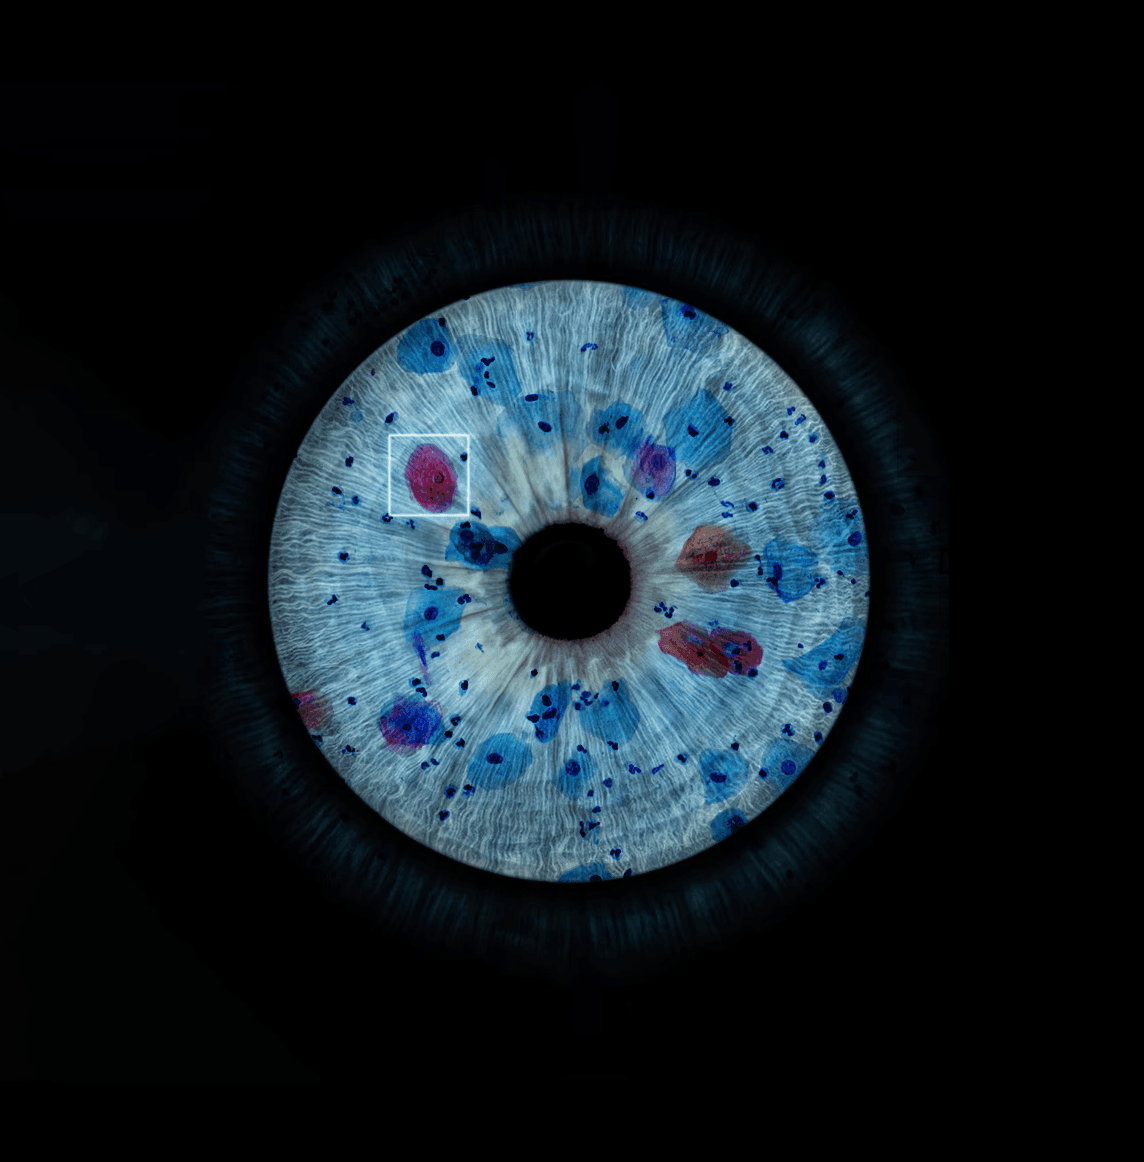

With Cytoprocessor® and its artificial intelligence, we bring the laboratory workflow to a new world of digital pathology.

With Cytoprocessor® and its artificial intelligence, we bring the laboratory workflow to a new world of digital pathology.